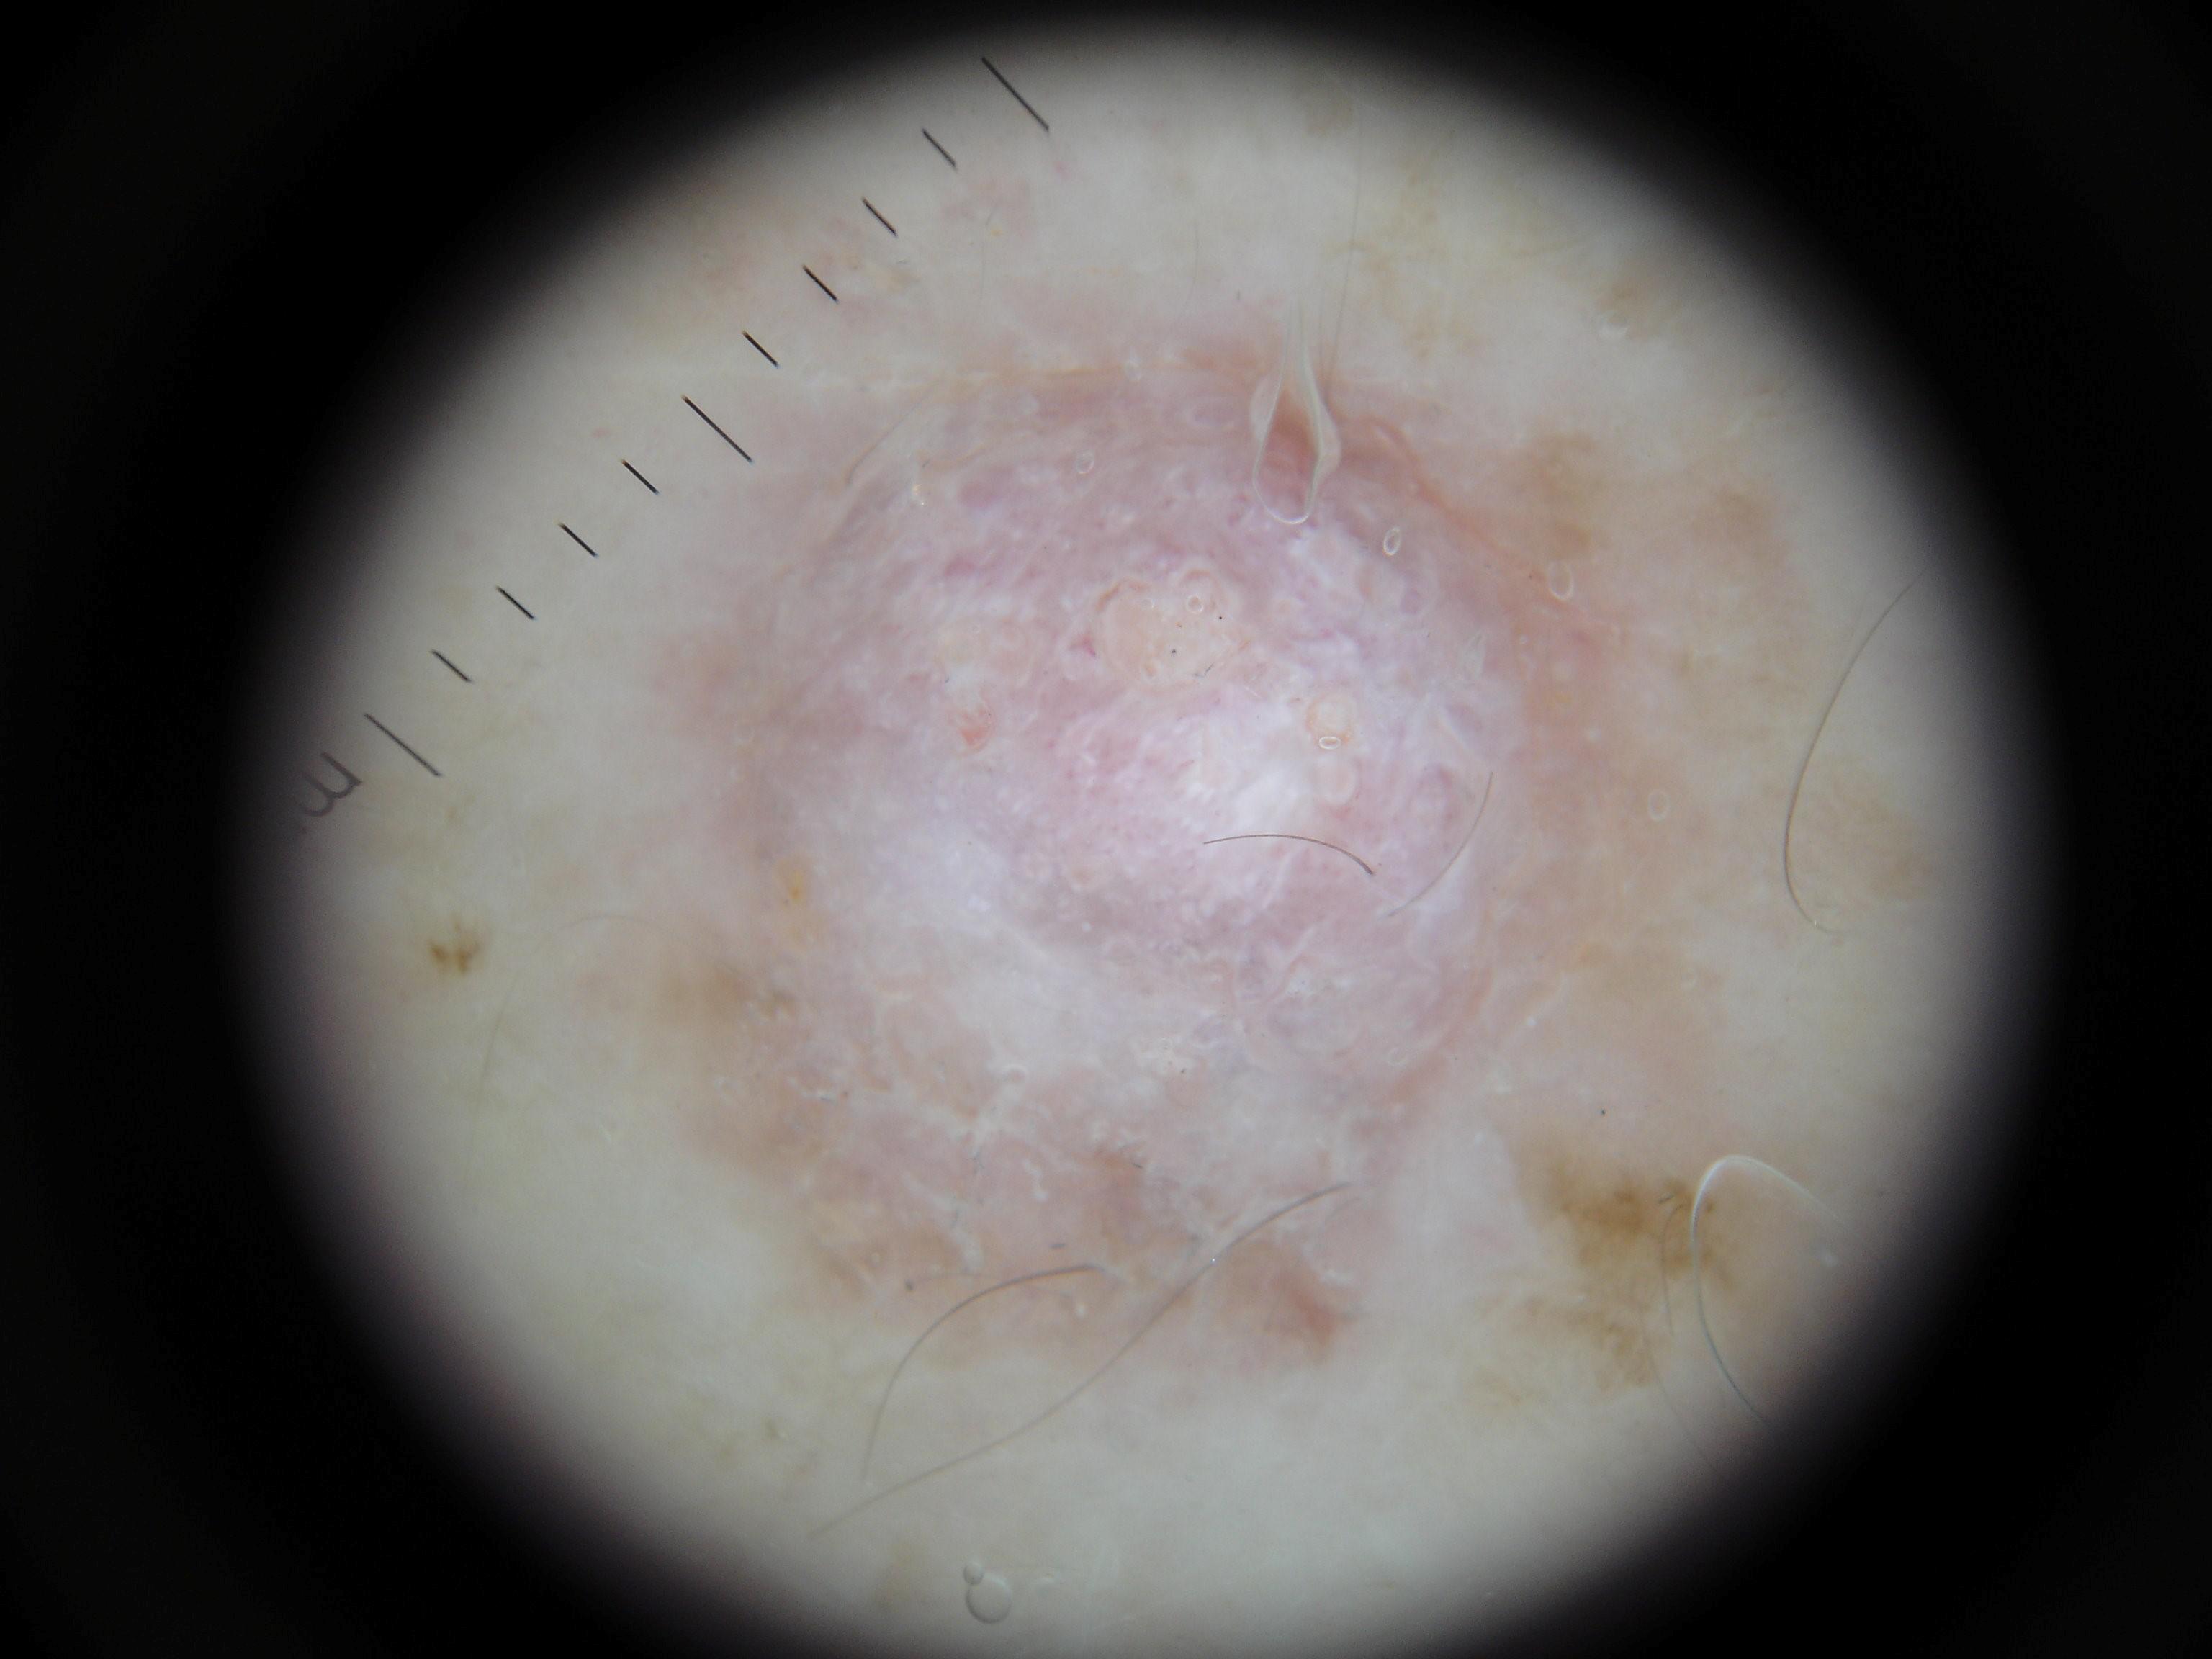

Biopsy-confirmed melanocytic and non-melanocytic skin lesions. This dataset includes over 500 melanomas. Many images have polarized and contact variants.